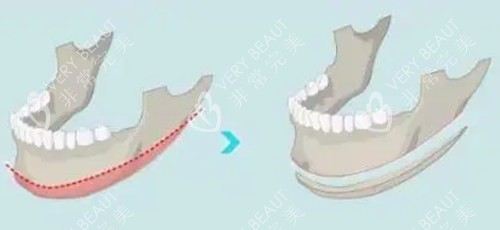

术前沟通时,刘医生没有急于推销方案,而是让我躺进CT扫描仪。半小时后,他指着屏幕上旋转的3D头骨模型说:"你的下颌角转折点偏低,但骨质厚度适中,适合做长曲线截骨。"更神奇的是,他拿出根据我颌骨数据打印的透明导板,严丝合缝地贴在我的下颌模型上,连神经血管走向都清晰标注。这种精密度让我悬着的心落了地——传统手术靠医生经验估算,而3D打印技术让每一毫米的截骨量都经过科学计算。

转折点出现在术后第20天。当我终于能拆下头套洗脸时,镜中的自己让我愣住了——曾经棱角分明的下颌线消失了,取而代之的是一条从耳垂到下巴的柔美弧线。更惊喜的是,刘医生在截骨时特意保留了"下颌角生理转角",避免一刀切造成的"蛇精脸"。这种"源于自己而优于自己"的设计,正是他倡导的"生态长曲线"理念。